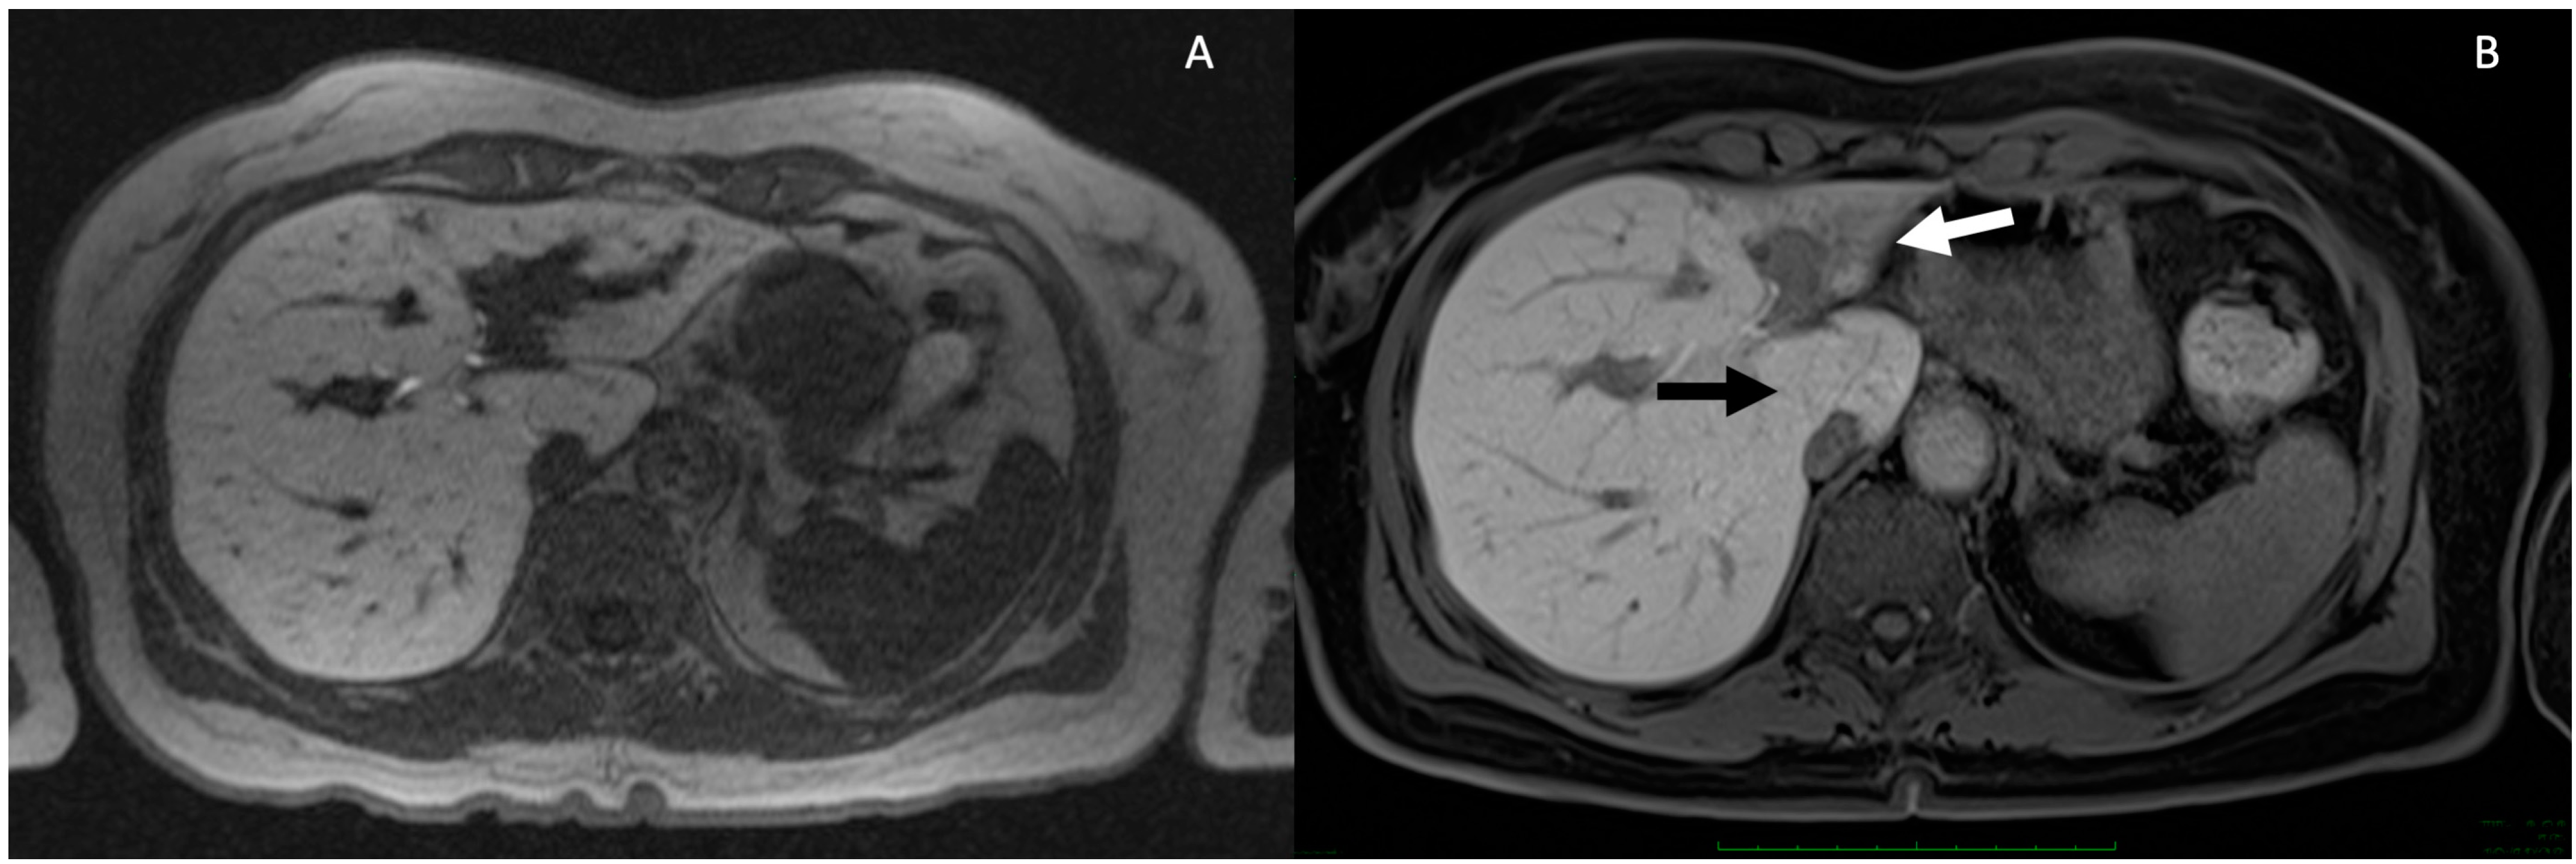

5. Technical Aspects of MRI in PSC

6. Cholangiographic and Liver Parenchymal Changes in PSC